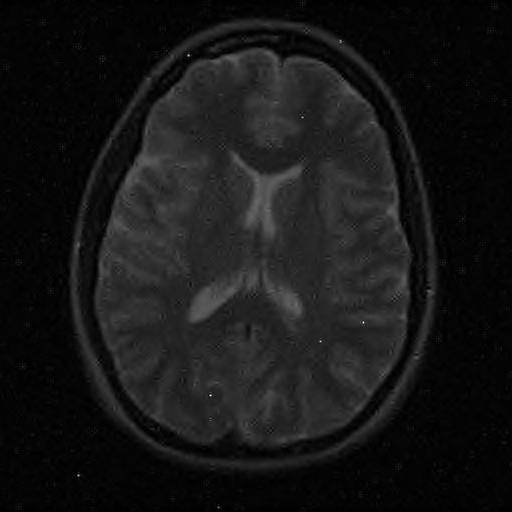

6.3. MR Image reconstruction

The second imaging application is concerned with medical imaging. Following the ideas from [32, 34], we simulate a multi-channel MRI sensing set-up, first using the same sine waves as in the previous experiment (results displayed in Fig 10), and then using spherical beam pattern (see in Fig. 11 for the results). We generate the classical Shep-Logan phantom, and set its dimension to .

The first experiment, depicted in Fig. 10 shows the results obtained by our method when using a Daubechies 4 sparsifying dictionary. Our results are compared to the single sensor analysis, and the results obtained by the Sum-of-Squares recovery [34, 32].

The recovery is obtained from noisy measurements, in which some additive Gaussian noise with variance has been added. The measurements are obtained by subsampling ( samples) of the Fourier transform. We see here that the fused compressed sensing is better capable of handling a multi-channel problem with unusual illumination (compared to the Sum-of-Squares method). Moreover, more details are preserved, when compared to the single sensor analysis method.

Some noise still appears in the image, but can easily be thresholded further if needed. One important aspect of MR Images that hasn’t been considered in this research, is the fact that they are sparse in gradient. One usually prefers to minimize the Total Variation instead of the norm or another frame using analysis.

Although we have not explicitly written the theory here, the recovered images in Fig. 11 show the results when using a TV minimization instead of the analysis.

| analysis | Sum of Square fusion | Fused analysis | |

|---|---|---|---|

| SSIM | |||

| PSNR | |||

| error |